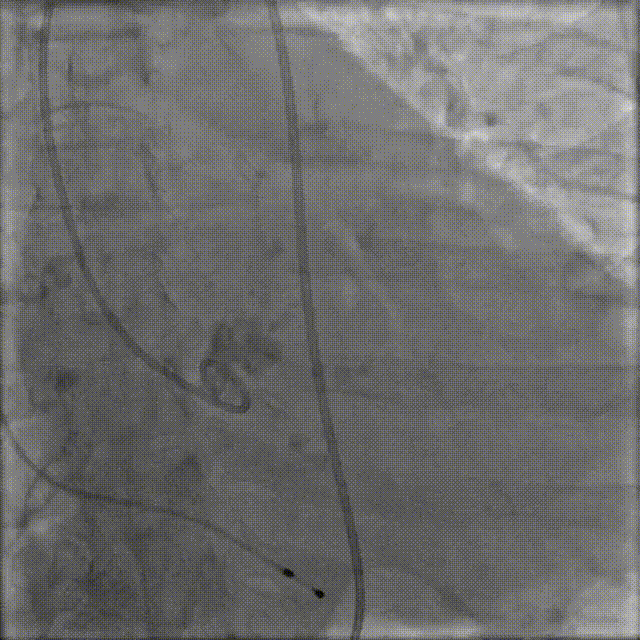

4.VitaFlow liberty™ TAV24瓣膜系统1:1等量精准释放

猪尾巴在无冠窦窦底定位,缓慢释放瓣膜,多次造影评估,实时观察冠脉显影情况.

释放到后1/3,多体位造影评估冠脉及植入深度

5.释放完成

瓣膜释放后造影提示冠脉⽆遮挡

最终瓣膜植入深度可,形态佳,⽆瓣周漏

术后即刻评估

术后行主动脉根部造影未见明显夹层,压差从145mmHg降至10mmHg,无明显瓣周漏,且冠脉血流通畅;复查心脏彩超显示心功能指标较前明显提升,症状明显改善。